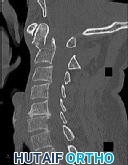

Figures 1 and 2 are CT scans obtained from a 68-year-old man who has had

progressive neck pain and stiffness, worsening gait imbalance, upper extremity weakness, early muscle fatigue, difficulty with fine motor control, and difficulty with activities of daily living over the past few years. On physical examination, he has a wide based stiff legged gait, generalized upper extremity weakness, dense sensory loss in the upper and lower extremities, and markedly brisk reflexes. What is the most appropriate treatment for this patient?

4. Posterior cervical laminoplasties from C3-6 Discussions: D

This patient has progressive myelopathy secondary to ossification of the posterior longitudinal ligament. Diagnostic imaging reveals multilevel cervical cord compression from C4-6. The patient has maintained reasonable cervical lordosis. A posterior procedure such as multilevel laminoplasty

decompresses the spine, is motion preserving, and has a low complication rate. Observation and cervical epidural injections are not viable options in patients with progressive myelopathy. Anterior cervical decompression, including corpectomy, is an option; however, anterior procedures have an increased risk of complications such as dural tear or cerebrospinal fluid leak. The axial CT image shows a "double layer" sign, which is consistent with dural ossification and increases the risk of dural injury with anterior decompression